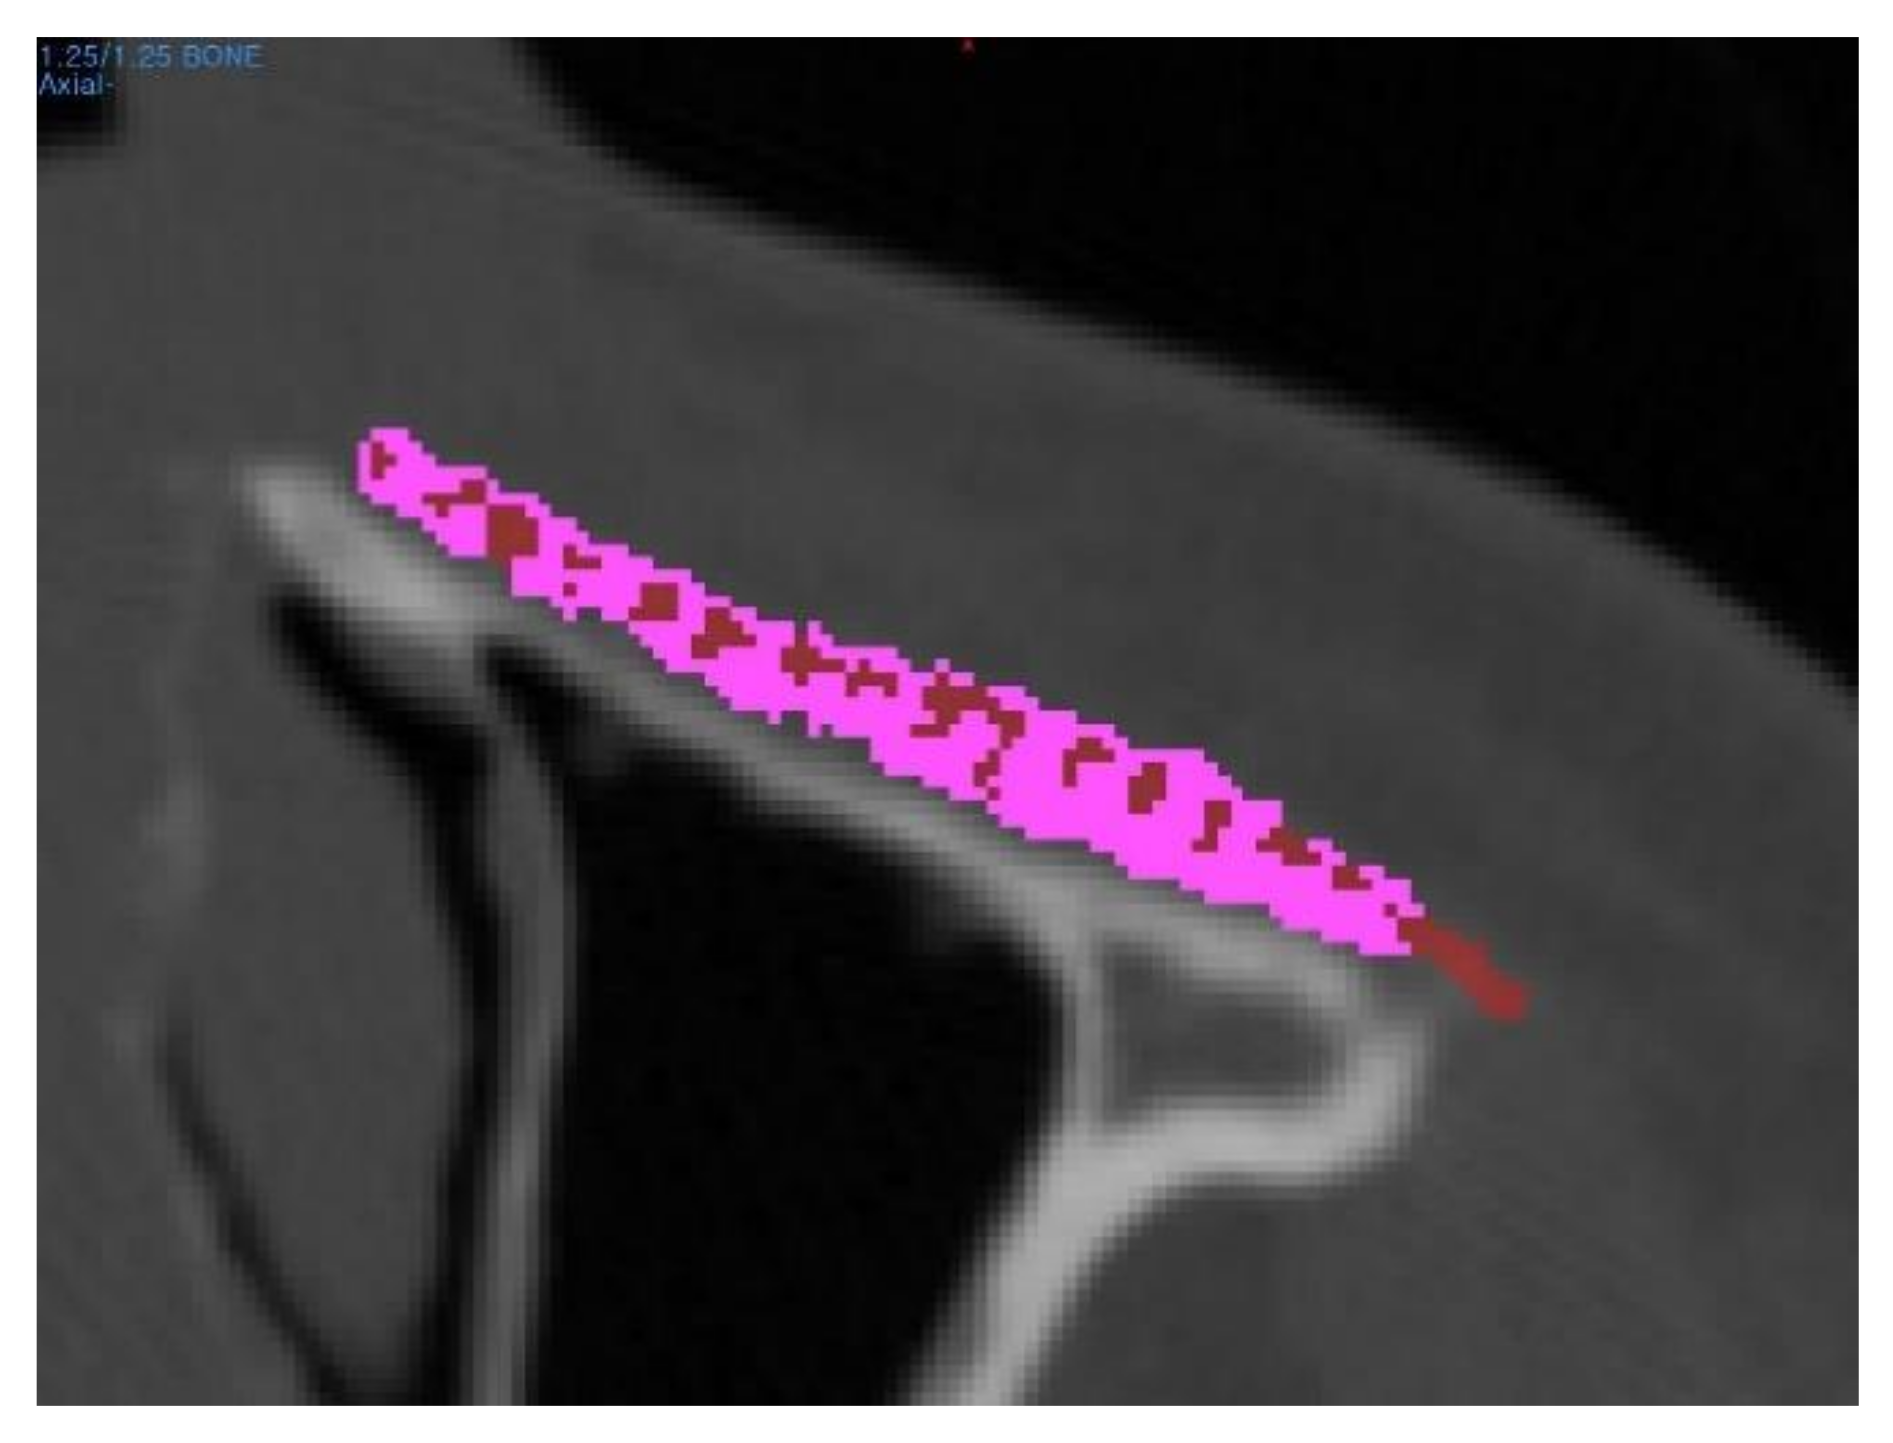

Figure 4. The bone volume fraction was defined as a ratio of the de novo bone volume to the total implant volume within the region of interest. Red area notes the region where the tissue density was measured over 200HU, while the purple area denotes the PCL/β-TCP scaffold.

To identify de novo bone formation, the CT images were subjected to radiodensity analysis using a 3D modeling software (Mimics, Materialise Software Solutions, Leuven, Belgium); the radiodensity was measured in Hounsfield units (HU) in the region of interest. The applied threshold to measure the bone mineral density of newly regenerated bone was 200 HU. The bone volume fraction was defined as the volume ratio of de novo bone to the total implant within the region of interest (Figure 4). In addition, the mean tissue density of the region of interest was investigated at different time periods, including before surgery and six months after surgery.